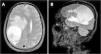

A 58-year-old male recycling worker was admitted to the emergency department with sudden-onset left-sided hemiparesis and altered mental status, prompting an initial evaluation for acute stroke. The patient also had a one-year history of progressive cognitive impairment, confusion, behavioral changes, and weight loss, with a BMI of 16.45 kg/m2 upon admission. Brain magnetic resonance imaging revealed a large intra-axial expansile lesion centered in the right parietal lobe, predominantly cystic and necrotic in appearance, containing fluid-fluid levels and a diffusion restriction component in its posterior aspect, suggestive of an abscess (Fig. 1).

Axial T2-weighted MRI (A) shows a lesion measuring 5.9 × 5.4 × 5.4 cm (CC × LL × AP) and exerts a compressive effect on the brain parenchyma, with hyperintense areas in the white matter secondary to vasogenic edema, accompanied by subfalcine herniation and right uncal herniation into the suprasellar cistern. There is an approximate 1.7 cm midline shift to the left. Peripheral rim enhancement without surrounding capsule irregularity is observed, findings that are suggestive of a tuberculous abscess rather than a pyogenic one. Sagittal MRI on T1 complements the visualization of the lesion (B).